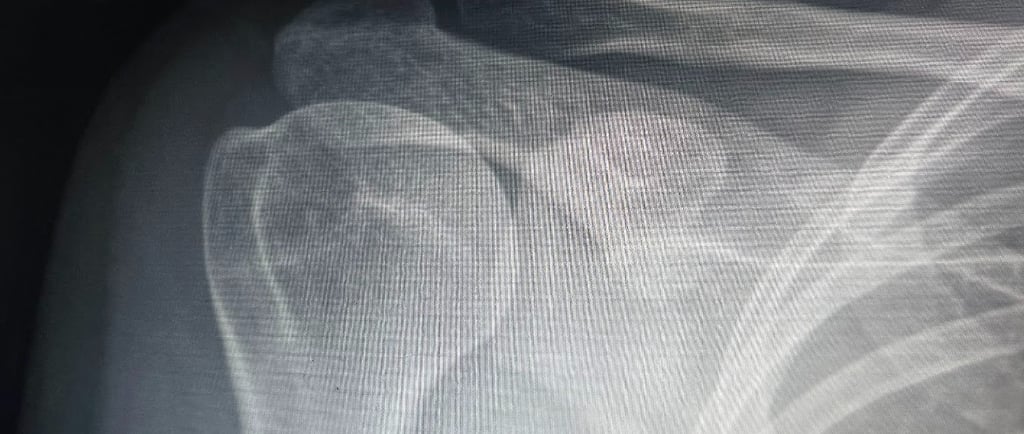

• Fracturas: Golpes o caídas pueden ocasionar fracturas en la clavícula, el húmero o la escápula, resultando en dolor severo y limitación de movimiento.

Para identificar la causa exacta del dolor de hombro, es necesario realizar una evaluación médica completa. El especialista llevará a cabo una exploración física para evaluar el rango de movimiento, la fuerza y la estabilidad de la articulación.

Además, pueden solicitarse estudios de imagen para observar el estado de los huesos, los músculos y los tejidos blandos. En algunos casos, se requieren pruebas de laboratorio para descartar enfermedades inflamatorias o infecciones que puedan estar afectando la articulación.